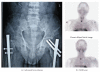

Primary hyperparathyroidism (PHPT) has become an asymptomatic disease in the Western world with the introduction of routine calcium screening. However, the same phenomenon is not observed in India. We have now systematically reviewed the status of PHPT in India. While there is a paucity of literature on PHPT from India when compared to Western countries, some information can be gleaned upon. Most patients present with symptomatic disease whereas very few are screen-detected cases (bone disease 77%, renal disease 36%, and 5.6% asymptomatic). Mean calcium, parathyroid hormone (PTH), and alkaline phosphate levels are high while Vitamin D levels are low. The average parathyroid gland weight is large and the majority being parathyroid adenomas (89.1%). Hungry bone syndrome (HBS) is common in the postoperative period. The disease-related mortality rate is 7.4%, recurrence 4.16%, and persistent disease 2.17%. We suggest that dedicated efforts are needed to pick up asymptomatic disease in India by methods like incorporating calcium estimation in the routine health check-up programs.